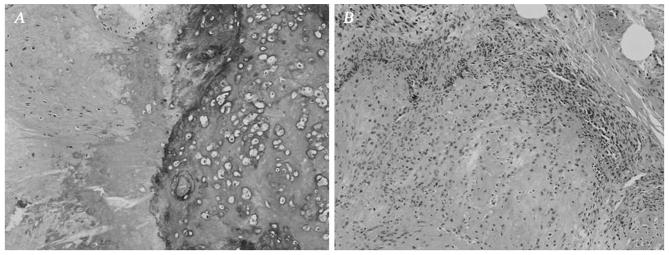

In the bone of the maxilla, the mass exhibited the morphological characteristics of a typical chondroblastic osteosarcoma. The tumor contained a relatively equal distribution of abnormal osteoid and chondroid, intimately associated with anaplastic tumor cells (Fig. 5A). Islands of osteoid were observed within the cartilage. The tumor bone exhibited a woven or basket weave pattern and was strongly hematoxylinophilic, unlike the uniform lamellar pattern of normal bone. The cartilage displayed malignant-appearing cells in lacunae, and there was crowding at the periphery of the lobule, where spindle cells were arranged in sheets (Fig. 5B).

Figure 5.

The histological appearance of the tumor in body of the left maxillary bone suggested a typical chondroblastic osteosarcoma. (A) The tumor contained deposits of hypercellular cartilage and abnormal osteoid and bone. (B) There was crowding at the periphery of the lobule, where sheets of atypical, pleomorphic and hyperchromatic sarcomatous cells were formed. Hematoxylin and eosin staining; magnification, ×10.